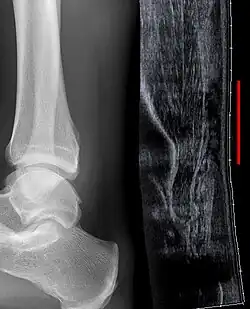

Zum Ausschluss eines knöchernen Ausrisses am Calcaneus sollte eine Röntgenaufnahme (OSG seitlich) erfolgen. Ergänzende Untersuchungen zur Abklärung einer möglichen Ruptur sind Ultraschall und MRT:

Der Vorteil der Sonographie ist die dynamische Untersuchungsmöglichkeit unter funktioneller Beanspruchung. Anhand des Untersuchungsbefundes kann mit der Distanz zwischen den beiden Sehnenenden eine Entscheidung zum Therapieverfahren getroffen werden: Nur geringe Distanz erhöht die Erfolgswahrscheinlichkeit einer funktionell-konservativen Behandlung. Bei großer Distanz sind operative Verfahren zu bevorzugen.

Sollte der Befund auch im Ultraschall nicht sicher beurteilt werden können oder auch bei untypischer Anamnese (ohne adäquates Trauma), ist die Durchführung einer Kernspinuntersuchung (MRT) eine weitere Option: Hier können gut frische, aber auch veraltete Rupturen, Degenerationen wie Kalkeinlagerungen und Teilrupturen nachgewiesen werden. Im Regelfall kann die Diagnose jedoch durch die Anamnese und die klinische Untersuchung gestellt werden.